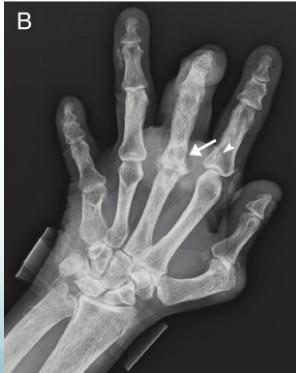

X-rays

- Which bone, and which site in bone?

- Solitary or multiple?

- Bone forming or bone eating?

- Margins: well-defined or ill-defined?

- Calcifications in the lesion?

- Is cortex eroded or destroyed?

- Is there periosteal new bone formation?

- Soft tissue extension?